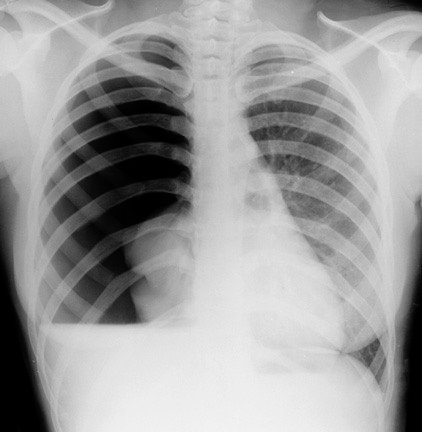

Tension pneumothorax

• Traumatic punctured lung wound acts as a one-way valve.

• Each inhalation- additional air accumulate in pleural space.

• Normal negative intrapleural pressure becomes positive.

• Depressing the ipsilateral hemidiaphragm.

• Pushing mediastinal structures to other side.

• Compressing contralateral lung.

• Heart rotated about the superior and inferior vena cava

• Venous return and cardiac output decreased.

(Image: Tension pneumothorax Needle decompression Intercostal tube)